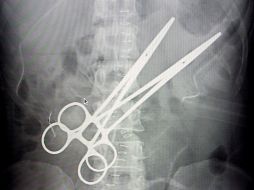

Tecnología Retiran a boliviana pinzas de 16 centímetros que médico dejó en su abdomen 21 de enero de 2012 - 18:44 hs Sanidad Ciencia médica